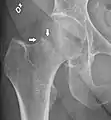

الأشعة السينية على الفخذ المصاب عادة ما تجعل التشخيص واضح، وينبغي الحصول على صور أشعه أماميه خلفيه وجانبيه.

في الحالات التي يشتبه في وجود كسر الورك ولكنه ليس واضح على الأشعة السينية، الاشعة المقطعية ثلاثية الابعاد (3D reconstruction) تكون مفيده للتشخيص. وقد اكتسب التصوير بالرنين المغناطيسي أهمية في تشخيص الحالات الغامضه من كسور رقبة عظمة الفخذ. في غضون 24 ساعة يمكن للتغييرات أن تري في التصوير بالرنين المغناطيسي. مسح العظام هو أقل فائدة لأنه قد يستغرق ما يصل إلى الاسبوع لإظهار التغيرات وخاصة في كبار السن.